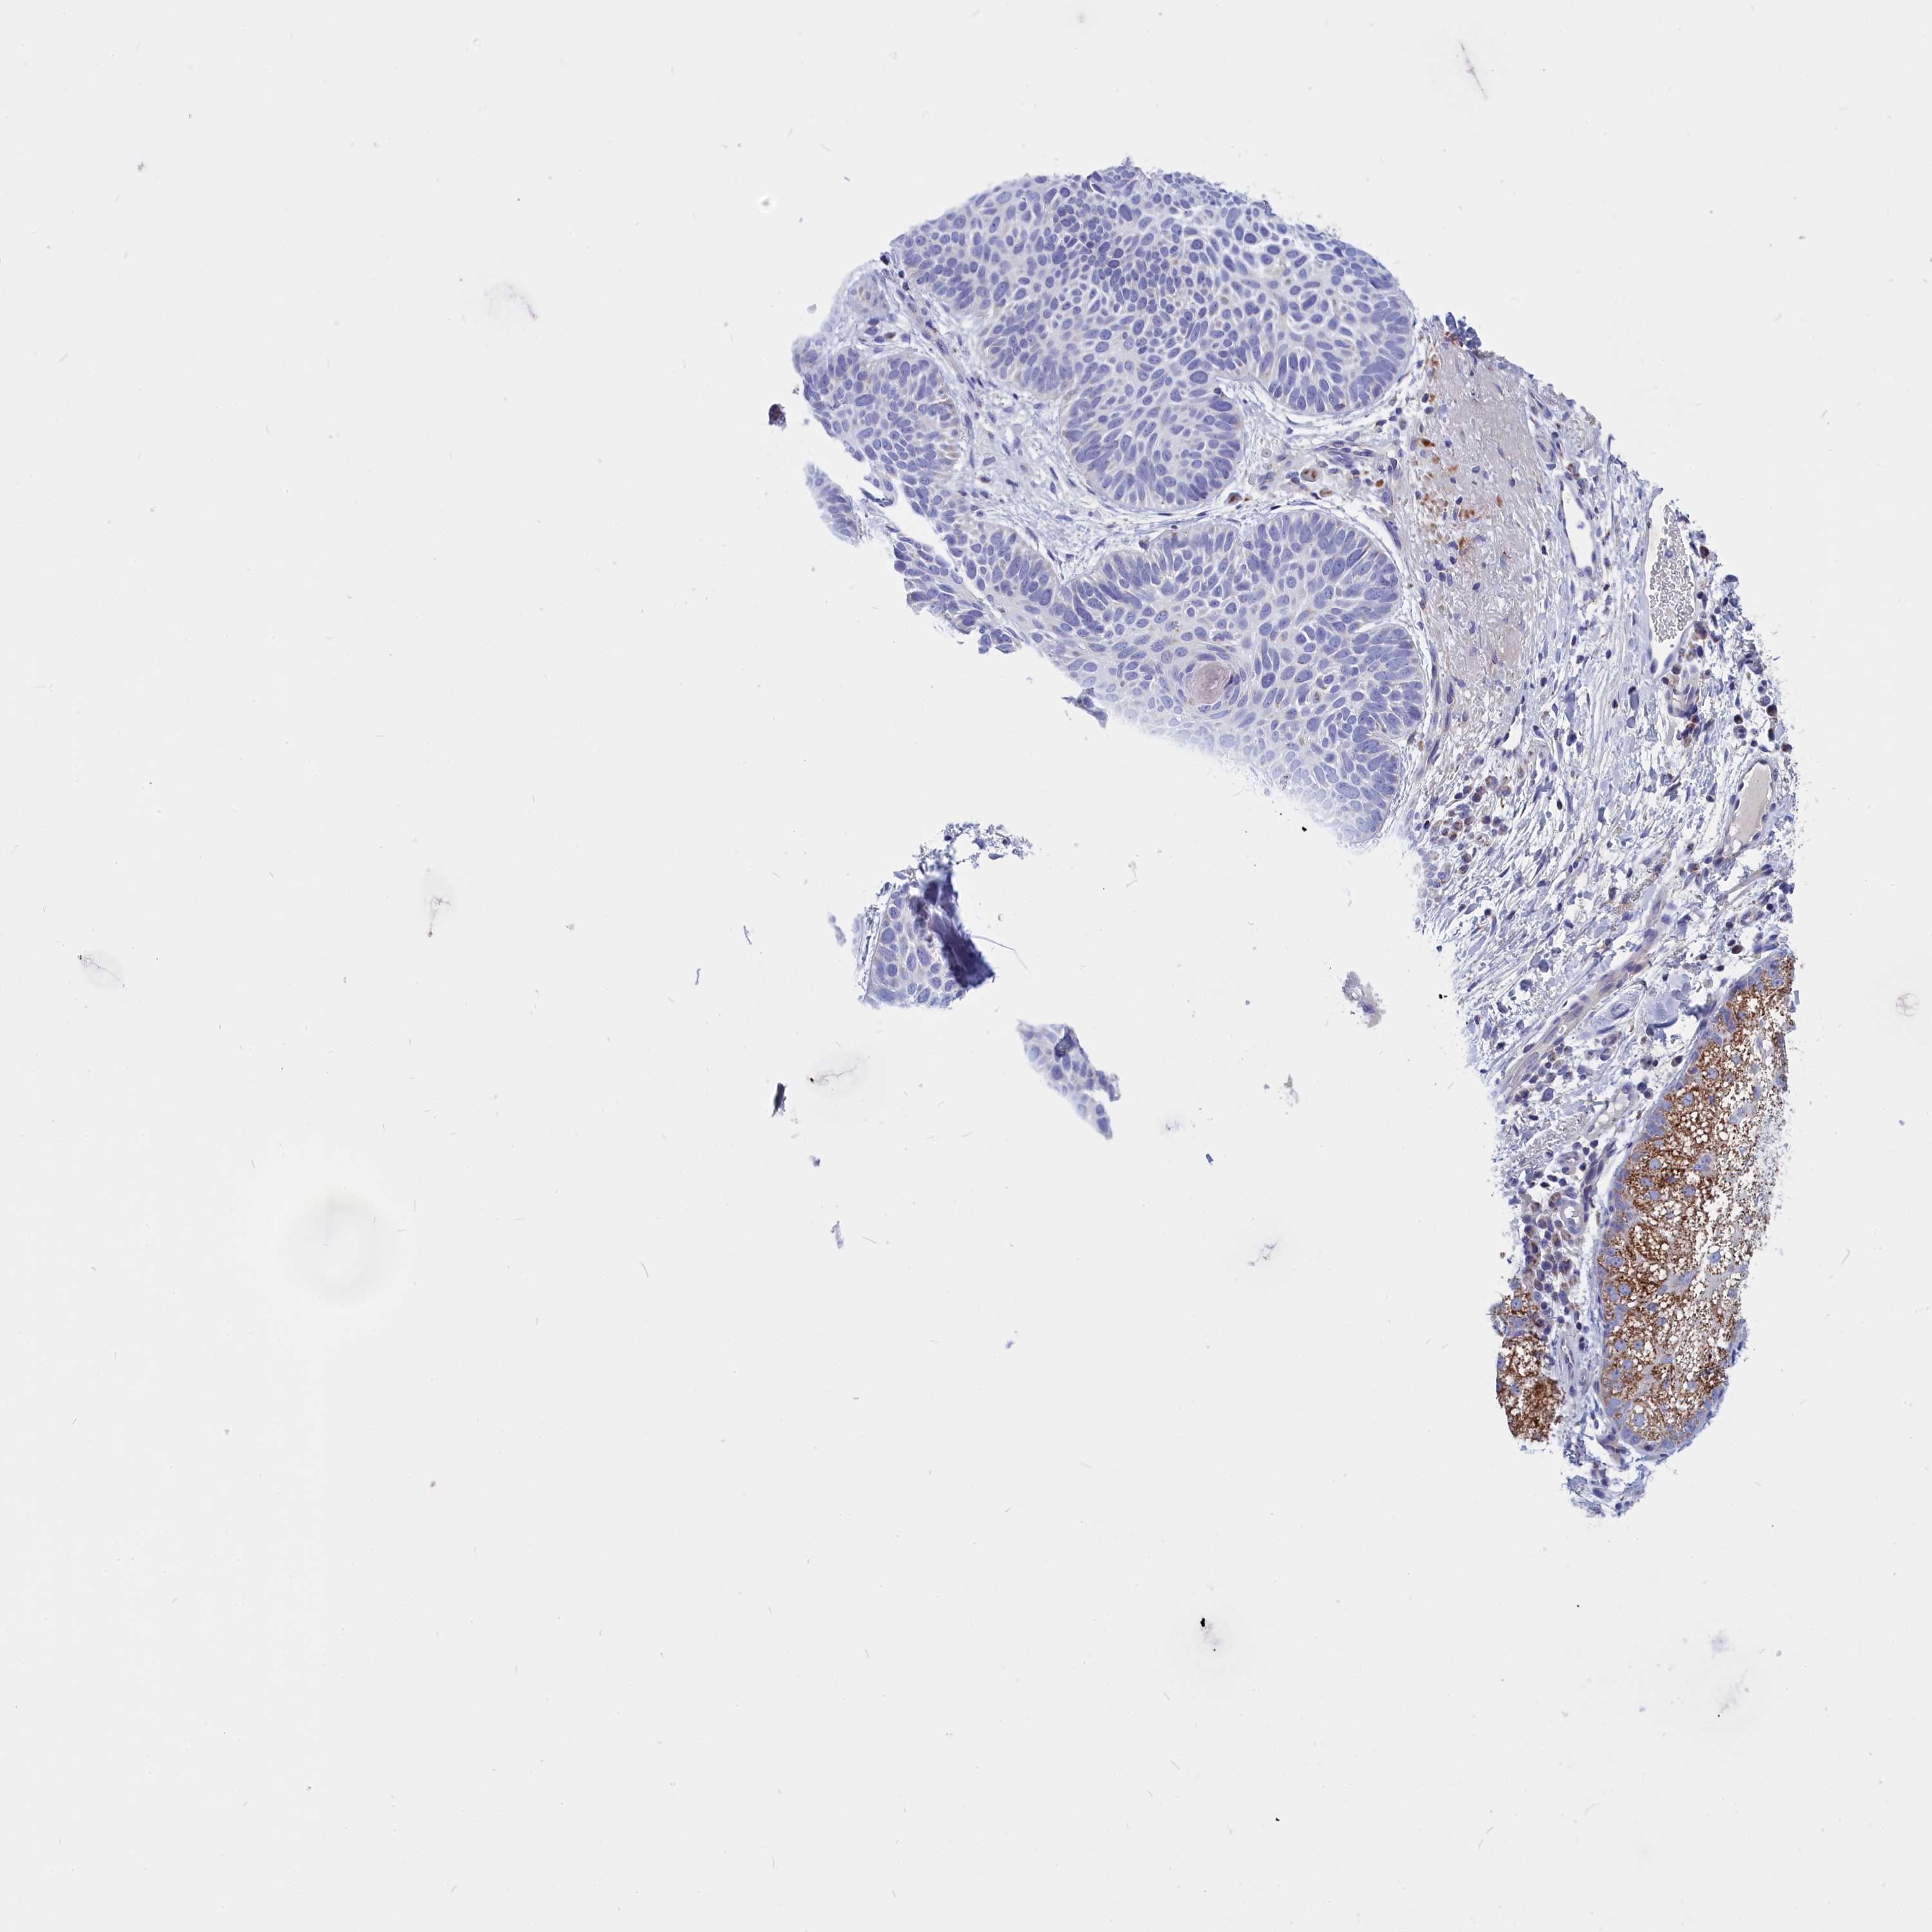

SKIN CANCER - Protein expressioni

A mouse-over function shows sample information and annotation data. Click on an image to view it in a full screen mode. Samples can be filtered based on level of antibody staining by selecting one or several of the following categories: high, medium, low and not detected. The assay and annotation is described here.

Antibody stainingi

Antibody staining in the annotated cell types in the current human tissue is reported as not detected, low, medium, or high, based on conventional immunohistochemistry profiling in selected tissues. This score is based on the combination of the staining intensity and fraction of stained cells.

Each image is clickable and will lead to virtual microscopy that enables deeper exploration of all samples and also displays staining intensity scores, fraction scores and subcellular localization as well as patient and tissue information for each sample.

Antibody HPA043238

Staining

High

Medium

Low

Not detected

Intensity

Strong

Moderate

Weak

Negative

Quantity

>75%

75%-25%

<25%

None

Location

Nuclear

Cytoplasmic/membranous

Cytoplasmic/membranous,nuclear

Basal cell carcinoma

Squamous cell carcinoma, NOS

Squamous cell carcinoma, metastatic, NOS